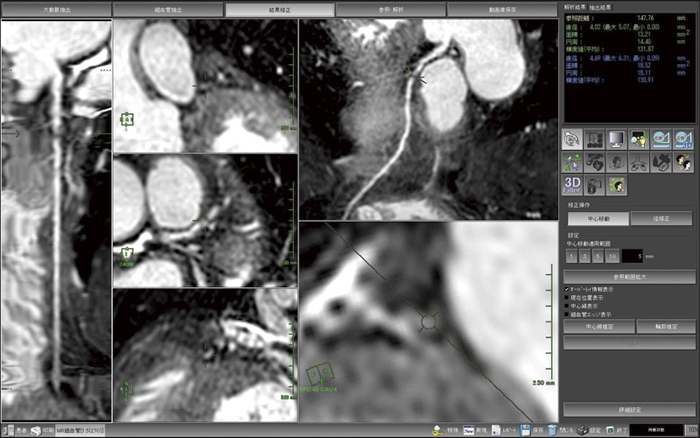

図1〜3は,MRIで撮像された冠動脈の解析結果画像である。図1はVR表示で,LAD#6に狭窄を見ることができる。図2の読影画面では,任意の部分にカーソルを合わせて,連動する複数のMPRによりその部分の詳細を確認する。図3のPWMIP表示では,末梢の血管を表示できるため,全体像の詳細な把握に有用である。また,血管外径を計測し,面積による狭窄率の計算も行うことができる。さまざまな表示方法を組み合わせ連動させることで,短時間で詳細な解析や読影を行うことができるものと考える。

図2 複数MPRとCPRによる読影画面

狭窄を多角的に観察する。